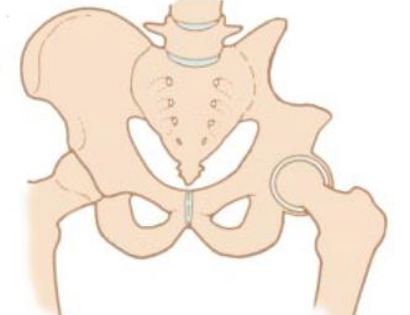

To reconstruct the hip after the tumor is removed, the gluteus medius muscle is attached to the abdomen as well as the adductors muscle. The sutures may be reinforced with surgical tape.

The gluteus medius muscle is attached to the prosthesis to ensure proper functioning post-surgically.

Multiple muscle rotation flaps are used to restore function and stability of the elbow as best as possible. The goal is to provide a stable hip so the extremity can function well. Soft-tissue reconstruction that involves rotating and reattaching the surrounding muscles, including the vastus lateralis, iliopsoas, and gluteus medius. Restoring the function of the surrounding muscles and hip joint is most important for achieving optimal functional outcomes and for protecting the prosthesis from infection.